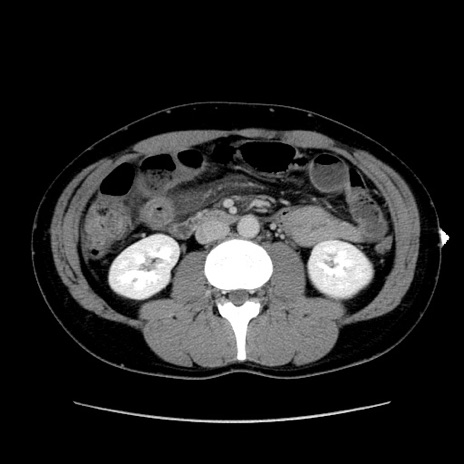

症例36(横断像)

【症例】20歳代 男性

【主訴】心窩部痛

【現病歴】今朝より上腹部痛あり。一旦軽快していたが再度出現したため救急要請。昨日夕に白身の魚を含む刺身を食べた。

【身体所見】BP 136/89mmHg、HR 74/min、BT 37.0℃、腹部:膨満、軟、心窩部に圧痛あり。反跳痛なし、筋性防御なし、腸雑音やや亢進あり。

【データ】WBC 17700、CRP 0.48